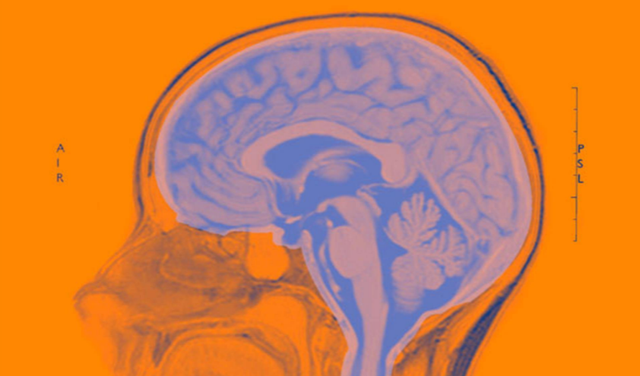

一、你必须了解大脑衰老的样子大脑的衰老是什么样子的?会有什么症状? 头发花白、步履蹒跚这些人体衰老状态我们一眼就能发现 , 而大脑的衰老“看不见”“摸不着” , 但是它却深深地影响着我们的生活 。

事实上大脑开始衰老的时间远超乎你的想象 。 人体的大脑在20岁的时候就开始走向衰老 , 直到40岁之后脑细胞减少到一定程度 , 就会出现一些实质性的症状 。 比如记忆力减退、健忘等症状 , 这种现象是一种大脑衰老的自然现象 。